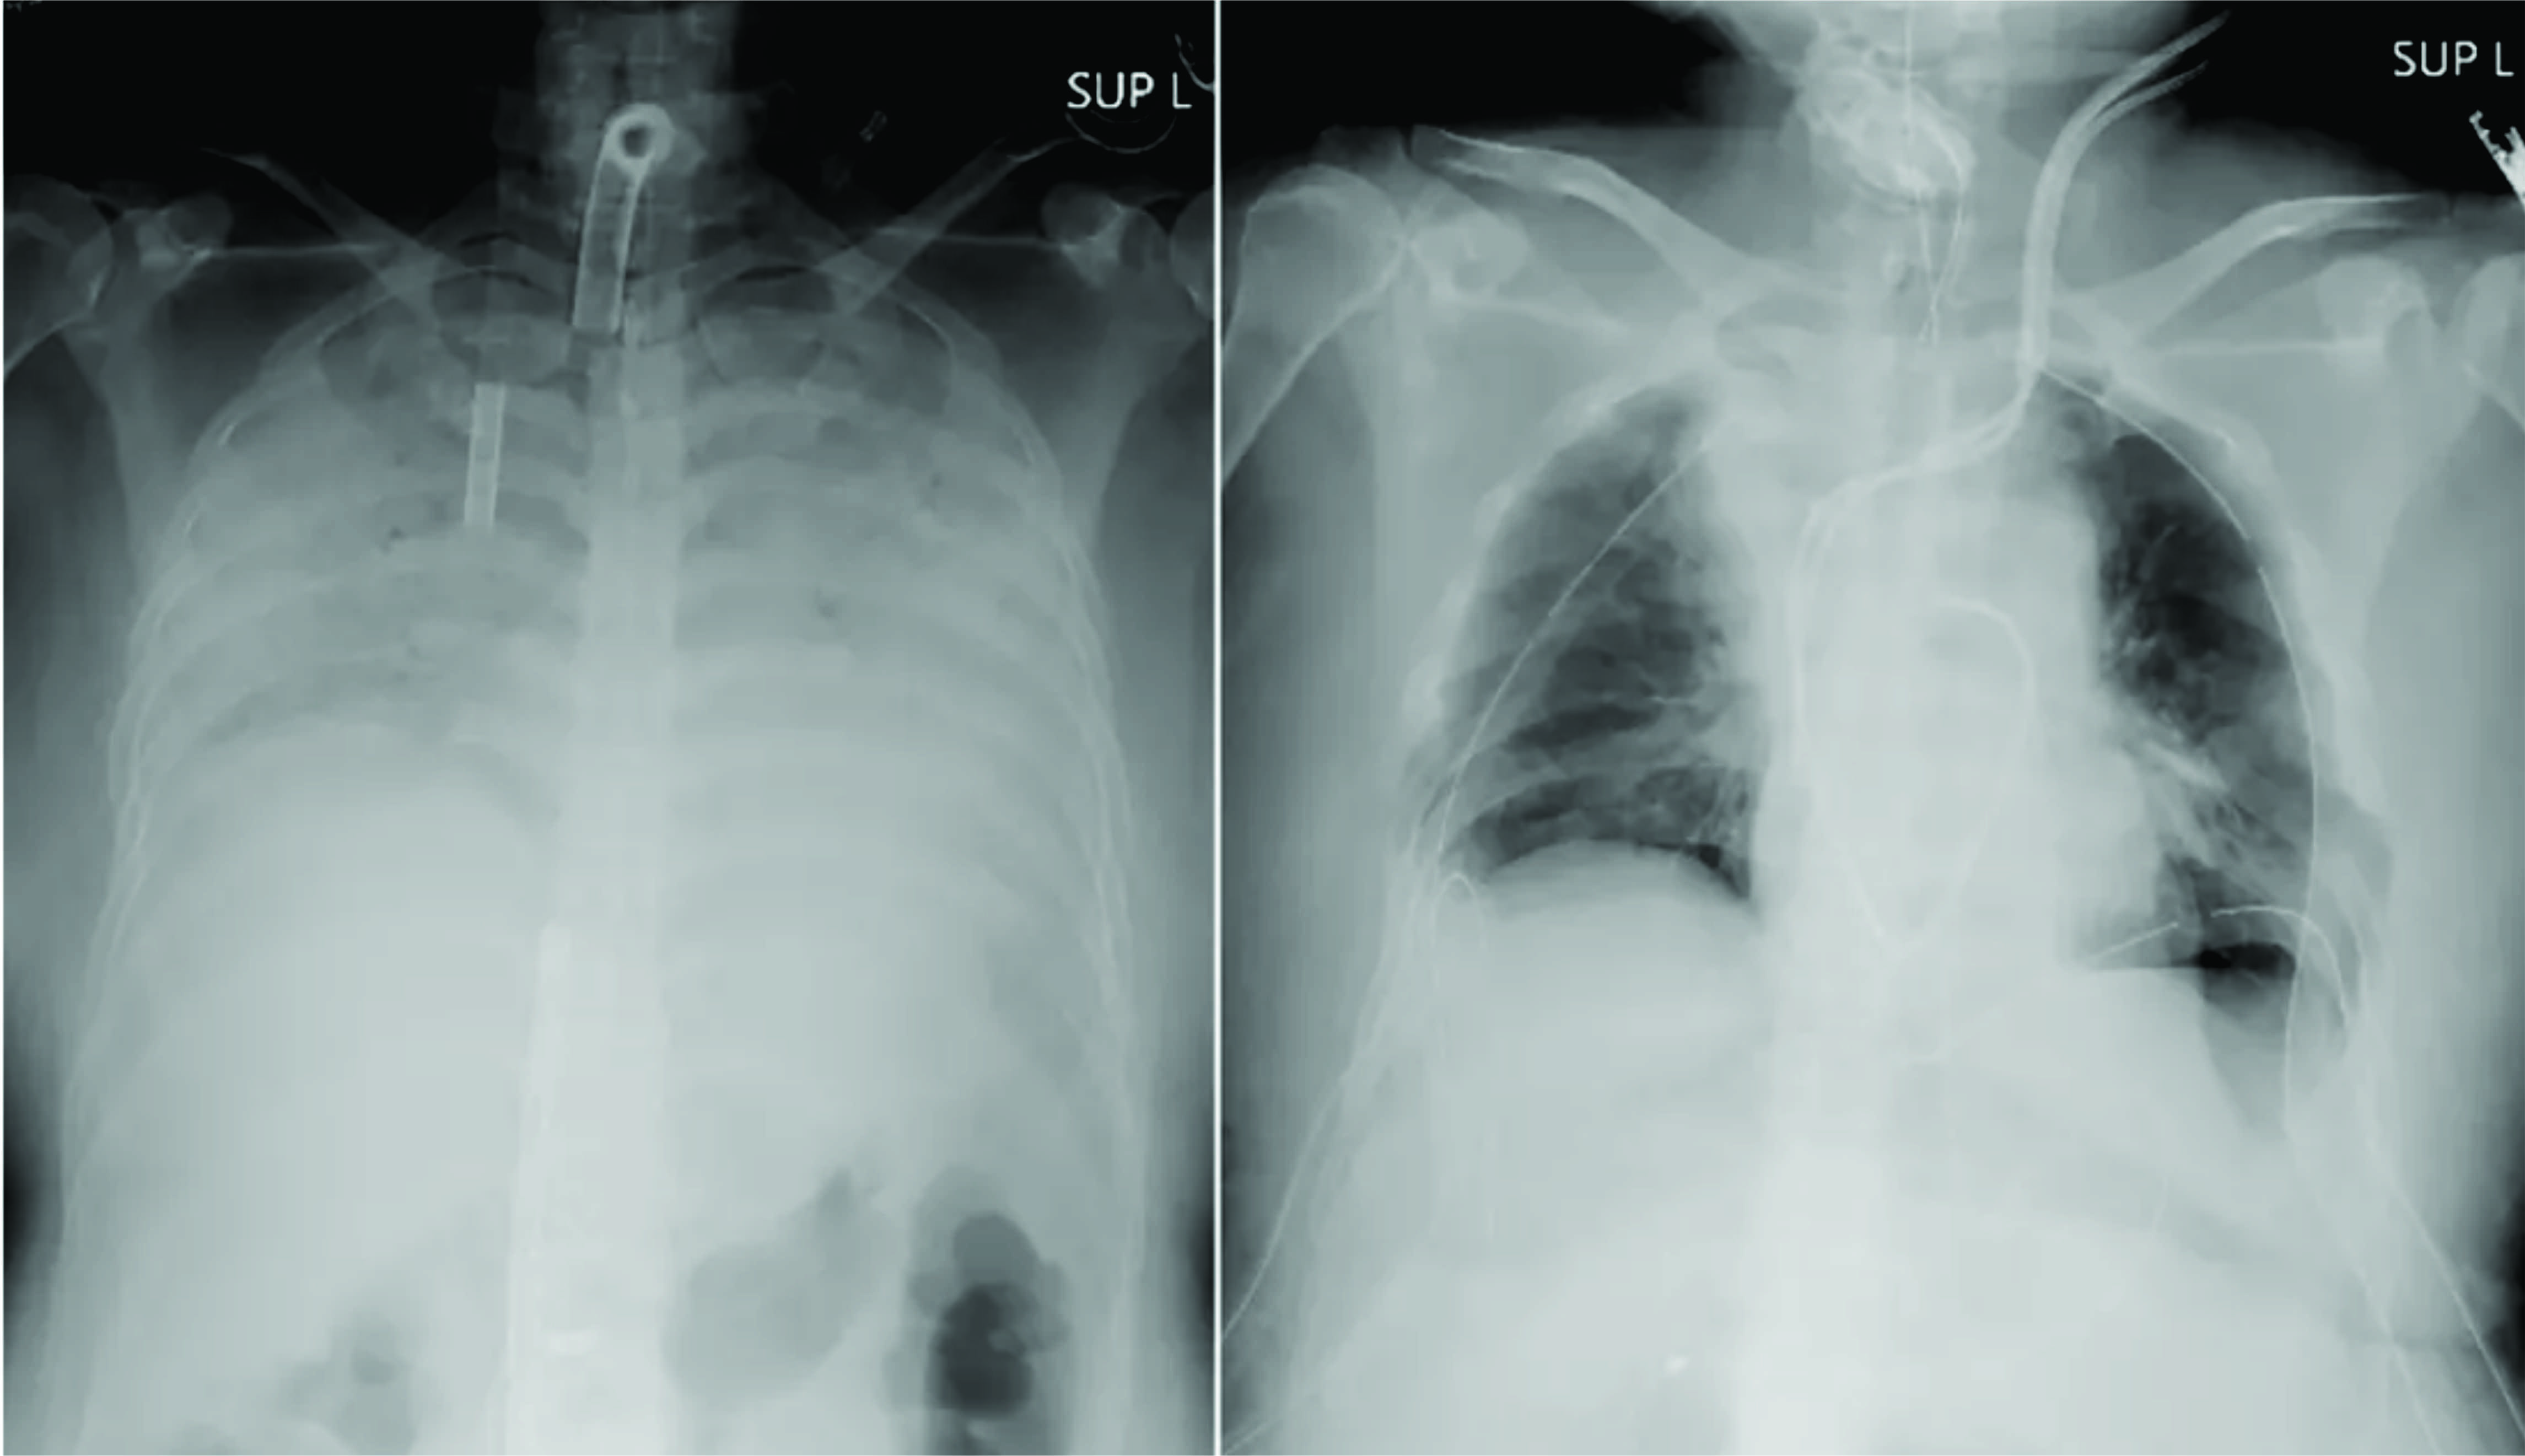

A mulher transplantada contraiu Covid-19 no final do ano passado e desenvolveu dificuldades respiratórias que pioraram rapidamente. Ela foi colocada em uma máquina de suporte de vida que funciona como um pulmão artificial por mais de três meses em um hospital porque seus pulmões estavam gravemente danificados.

A paciente se livrou do vírus, mas seus pulmões deixaram de ser funcionais ou tratáveis, e a única opção para ela continuar a viver era receber um transplante de pulmão, segundo a universidade.